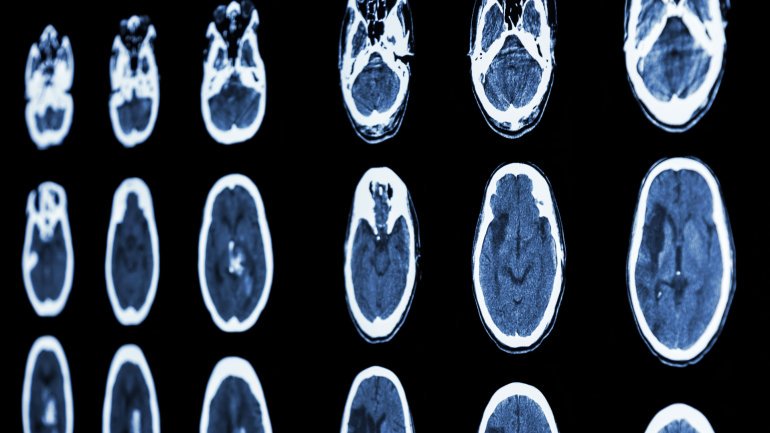

Pueden desencadenar ACV. Entre el 2 y el 6% de la población puede tenerlo y no lo sabe. Además, el 70% que sangran producen una discapacidad grave o la muerte. Cómo detectarlos y qué hacer.

El aneurisma cerebral puede desarrollarse sin que la persona sienta síntomas. Si no aparece como dolor de cabeza intenso o alteraciones vinculadas a la arteria, la persona puede pasar toda su vida desconociendo su existencia.

Sin embargo, si se los identifica se pueden tomar medidas para evitar que el aneurisma se rompa y desencadene lo que se conoce como ACV hemorrágico ya que está comprobado que el 70% de los aneurismas que sangran provocan discapacidad severa o mortalidad. Además, se estima que entre el 2 y el 6% de la población puede tener algún tipo aneurisma cerebral y no saberlo.

Una de las razones de los ACV hemorrágicos pueden ser las rupturas de los aneurismas, por eso, si bien, la enfermedad no es hereditaria, los profesionales recomiendan a los familiares de las personas que ya padecieron de aneurismas, controlarse y estudiarse mediante técnicas de diagnóstico por imágenes no invasivas.

"En la actualidad disponemos de estudios no invasivos y sin riesgo para el paciente; el más indicado es la resonancia magnética, que puede ser complementado con una angiografía por resonancia", dijo Juan José Cirio, jefe de la unidad de ACV de la Clínica La Sagrada Familia. Y agregó: "En los casos de familiares con aneurismas recomendamos repetir estos estudios cada 10 años".